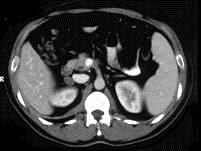

问题 女,23岁,满月脸、向心性肥胖,CT扫描如图所示,应诊断为 ( )

选项 A、右侧肾上腺嗜铬细胞瘤 B、右侧肾上腺转移瘤 C、右侧肾上腺腺瘤 D、右侧肾上腺腺癌 E、右侧肾上腺增生

答案 C